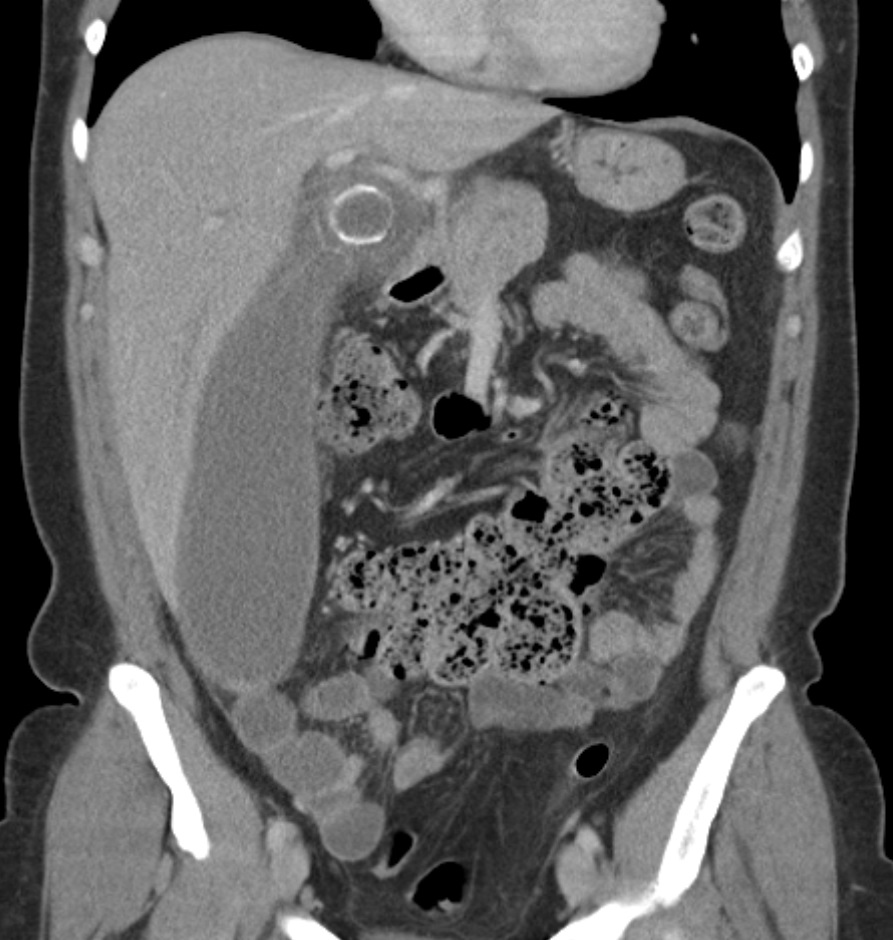

CT 스캔은 급성 충수염을 진단하는데 사용된다.[36] 의사는 환자의 병력과 증상을 평가하고, 신체 검사를 시행하며, 검사실 및 영상 검사를 모두 주문한다. 비전형적인 증상을 보이는 경우에는 초음파나 CT 스캔과 같은 영상 검사가 필요하다.[12] 소아는 방사선 노출 위험 때문에 초음파 검사를 우선적으로 시행하며, 결과가 불확실한 경우에만 CT 스캔을 추가로 시행한다.[54][55][56] 성인 및 청소년의 경우 CT 스캔이 초음파 검사보다 더 정확하며, 민감도 94%, 특이도 95%를 보인다. 반면 초음파 검사는 민감도 86%, 특이도 81%이다.[57]복부 초음파 검사, 특히 도플러 초음파는 특히 소아에게서 충수염 진단에 유용하다. 초음파 검사에서는 오른쪽 장골와에서 액체 저류, 컬러 도플러 사용 시 혈류 증가, 충수의 비압착성 등이 관찰된다. 급성 충수염의 다른 징후로는 충수 주변의 에코성 장간막 지방, 충수 결석의 음향 그림자 등이 있다.[58] 약 5%의 경우, 장골와 초음파 검사에서 이상이 발견되지 않지만, 이는 초기 충수염이거나 지방과 장내 가스로 인해 충수 확인이 어려운 성인에게서 흔하게 나타난다. 숙련된 검사자는 초음파 영상을 통해 충수염과 유사한 증상을 보이는 림프절 염증, 난소 또는 나팔관 문제 등을 구별할 수 있다.[60] 초음파 검사는 방사선과나 응급 의학 전문의가 시행할 수 있다.

컴퓨터 단층 촬영술(CT)은 병력 및 신체 검사에서 진단이 불확실한 경우에 자주 사용된다. 2019년 코크란 리뷰에 따르면 성인 급성 충수염 진단에 대한 CT의 민감도와 특이도는 높다.[62] 그러나 방사선 노출 우려로 인해 임산부와 어린이에게는 CT 사용을 제한하고, 자기 공명 영상(MRI) 사용이 증가하는 추세이다.[63][64]

충수염 진단은 충수 크기가 가장 중요하며, 6mm 이상이면 민감도와 특이도가 모두 95%이다.[65] 그러나 충수가 분변 물질로 채워져 팽창된 경우에는 진단이 어려울 수 있다.[66] 이 경우 초음파 검사가 유용하며, 주변 장에 비해 벽의 조영 증강, 주변 지방 염증 등의 특징으로 진단을 돕는다. 심한 경우 농성 염증, 고름집, 고름이나 장 내용물 누출로 인한 골반 내 액체 층이 관찰될 수 있다. 마른 환자는 지방 부족으로 충수와 주변 염증 관찰이 어려울 수 있다.[66]

CT 검사에서 충수 부종이나 주변 지방 조직 농도 상승이 관찰되며, 조영제 사용 시 민감도와 특이도가 모두 98%로 정확도가 높다. 최신 초음파 검사 장비는 맹장 형태 평가에 유용하지만, 맹장 위치나 장비, 검사자 숙련도에 따라 진단이 어려울 수 있다. 최근 소아 충수염 진단에서 컴퓨터 단층 촬영(CT) 검사는 감소하고 초음파 검사는 증가했지만, 임상 경과에는 변화가 없다는 보고가 있다.[126]